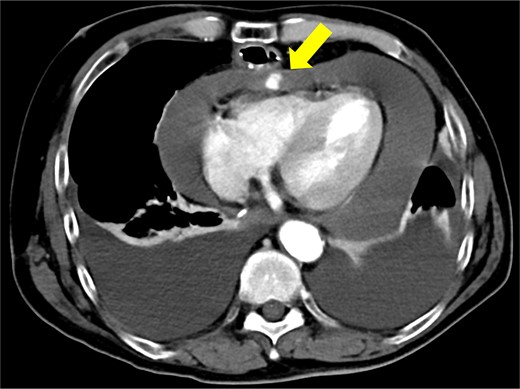

The patient underwent robotic subtotal esophagectomy, two-region lymph node dissection, narrow gastric tube was created by hand assisted laparoscopy and cervical anastomosis was performed via the retrosternal route. The operation took 613 min, with minimal blood loss. The retrosternal route under camera assist was created without bleeding, and no intraoperative hemodynamic changes or complications were observed. The pathological stage was pT1b(SM2)pN1M0 pStage II (Japanese Classification of Esophageal Cancer, 12th Edition). Esophageal fluoroscopy on postoperative day (POD) 7 showed a minor leak at the anastomotic site, which improved by POD 14 after cervical wound release and drainage. The minor leak at the anastomosis site has been the cause of prolonged hospital stay. The patient experienced sudden intermittent chest pain on POD 17, but his vital signs remained stable. Echocardiography revealed an increased amount of pericardial fluid. He was diagnosed with pericarditis and prescribed colchicine by cardiologist; however, pericardial fluid levels continued to increase. Pericardiocentesis with pericardial catheter insertion was performed on POD 34, revealing bloody pericardial fluid. Blood drainage persisted at approximately 300 ml/h. Urgent contrast-enhanced CT revealed contrast extravasation from the anterior right ventricle (Fig. 2). Coronary angiography revealed aneurysmal changes in the peripheral right ventricular branch without apparent hemorrhage (Fig. 3).

Contrast-enhanced computed tomography shows contrast extravasation in the anterior right ventricle (arrow).